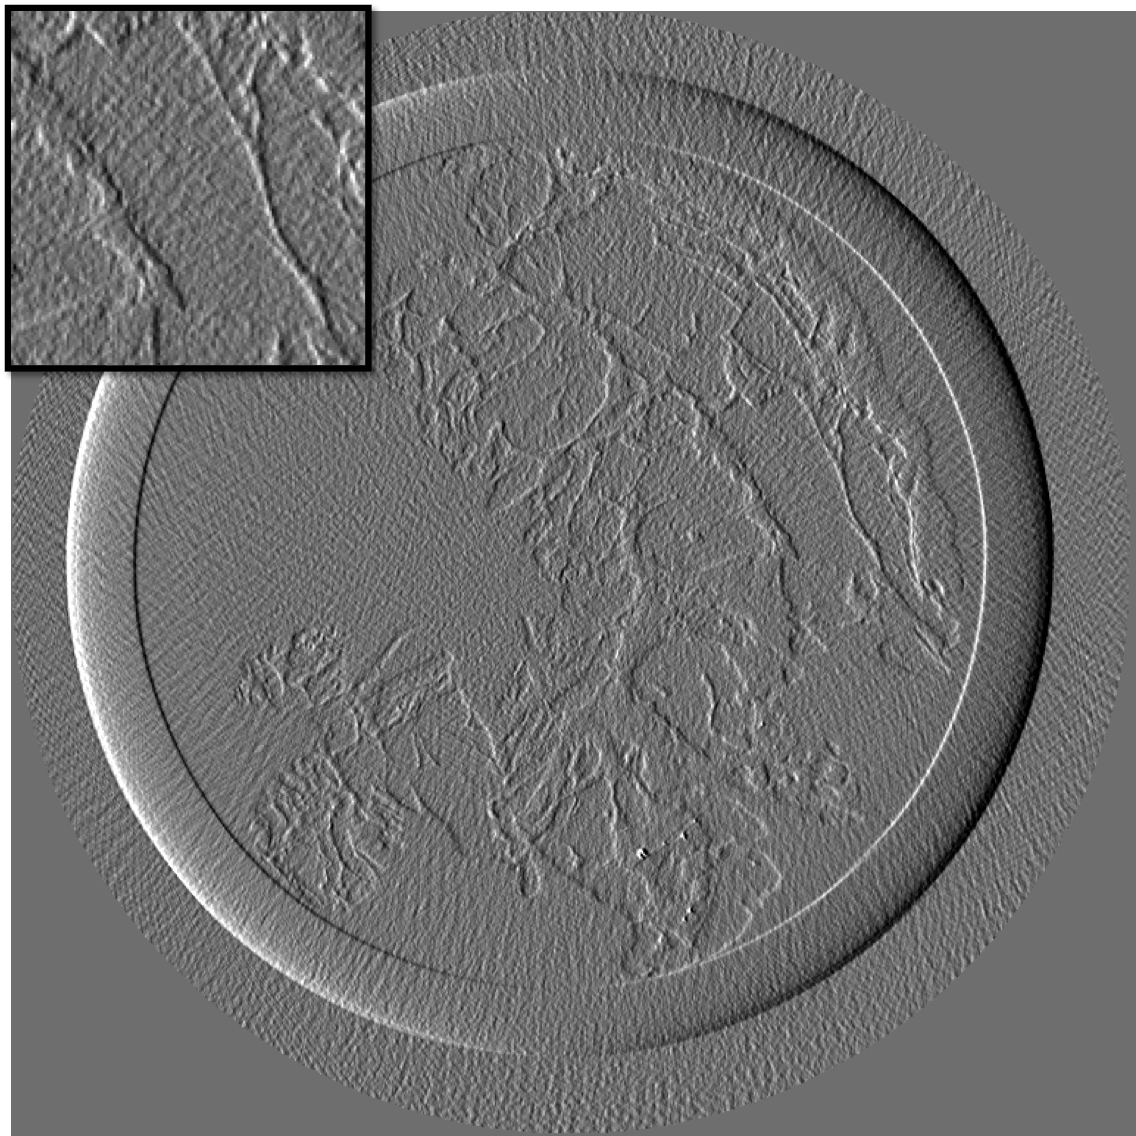

Figure 10 is the reconstruction for a pixels slice, using only 200 projections over the 1000 available. The upper left square is a zoom in the region marked in sub figure 10. The right column is the reconstruction with our method for X and Y components, while the left column is reconstructed with standard filtered back-projection using all 1000 available projections. Using our method we can still generate a high quality image with only one fifth of the projections which would be otherwise necessary to generate a high quality reconstruction with the standard FBP method. Visually the difference between the FBP results obtained with full data set and our method with a five-fold reduction of data is barely noticeable. The different borders of structures like skin layers, fatty tissues, and collagen strands are easily identified. The obtained result are very promising and a systematic evaluation for clinical application is under-way. The radiation dose absorbed by the sample during 200 projections is comparable to that of a standard clinical dual view (2D) mammography (3.5mGy).

For an eventual future clinical application of the PCI method it is important to investigate which is the acceptable compromise in terms of low dose and sufficient level of image quality. We need therefore to better explore how the quality of the reconstruction is degraded when we reduce the dose (i.e. number of projections and the acquisition time) further below the standard values. To this end, we performed a reconstruction with only 125 projections and results are shown in the figure III-D for one gradient differential image.

For an eventual future clinical application of the PCI method it is important to investigate which is the acceptable compromise in terms of low dose and sufficient level of image quality. We need therefore to better explore how the quality of the reconstruction is degraded when we reduce the dose (i.e. number of projections and the acquisition time) further below the standard values. To this end, we performed a reconstruction with only 125 projections and results are shown in the figure11. The first column present the result using our method, the second column is the result of reconstruction using FBP algorithm.

If a slightly higher noise level is tolerable, the method may be used with very few projections and thus applied to the screening and diagnosis of human breast cancers with an even lower radiation dose than conventional dual mammography. The results of our reconstruction show an image quality and a capability of discriminating fine structures that are still clinically acceptable. On the contrary, images produced with the standard FBP reconstruction method are very noisy and not diagnostically satisfactory.